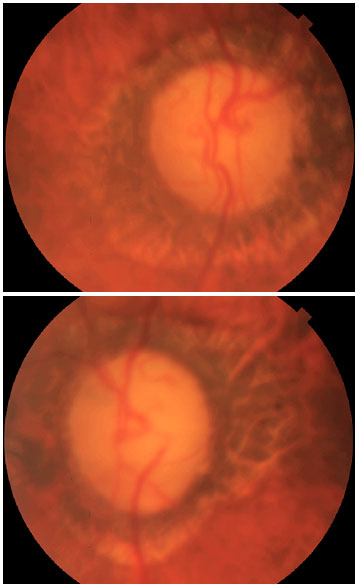

Anterior biomicroscopy revealed pseudoexfoliative material forming three zones on the anterior lens capsule OU (Figure 1). The patient also had 2+ nuclear cataracts OU. Gonioscopy revealed an open-angle Sampaolesis’s line and whitish material deposits (Figure 2) OU. Fundus examination showed a cup-to-disc ratio of 1.0 OU with peripapillary atrophy (Figure 3). Left eye achromatic automated perimetry demonstrated advanced visual field damage.